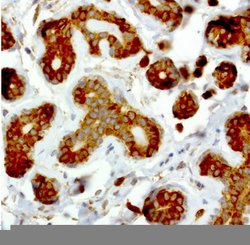

NME1 Mouse anti-Canine, Human, Rat, Clone: UMAB94, liquid, UltraMAB™

NME1 was identified because of its reduced mRNA transcript levels in highly metastatic cells. Nucleoside diphosphate kinase (NDK) exists as a hexamer composed of ′A′ (encoded by this gene) and ′B′ (encoded by NME2) isoforms. Mutations in the gene have been identified in aggressive neuroblastomas. Two transcript variants encoding different isoforms have been found for this gene. Co-transcription of this gene and the neighboring downstream gene (NME2) generates naturally-occurring transcripts (NME1-NME2), which encodes a fusion protein comprised of sequence sharing identity with each individual gene product.Specifications

| Immunocytochemistry, Immunofluorescence, Immunohistochemistry (Paraffin) | |